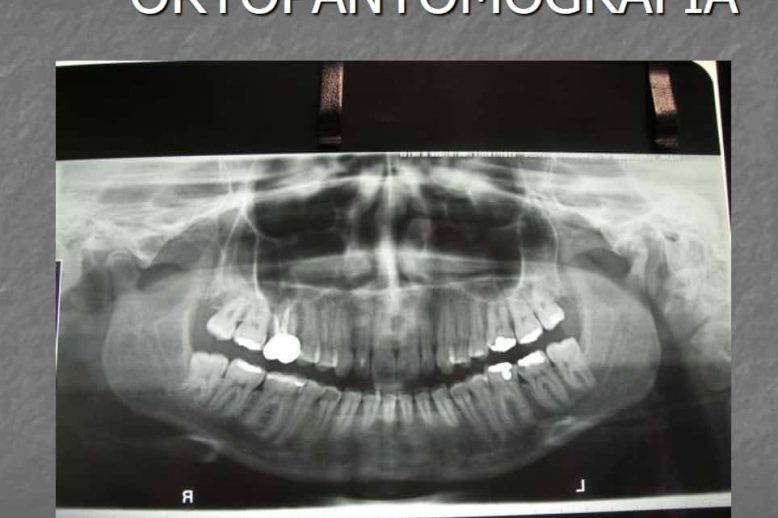

Trattamento conservativo dell’osteoartrosi dell’articolazione temporo-mandibolare: iniezione intra-articolare di sodio ialuronato

L’infiltrazione di ialuronato di sodio è risultata un valido trattamento non chirurgico per la malattia degenerativa dell’articolazione temporo-mandibolare